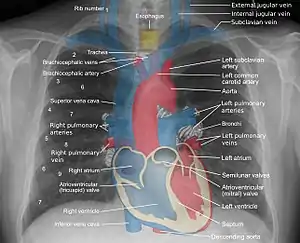

Chest radiograph

A normal posteroanterior (PA) chest radiograph of someone without any signs of injury. Dx and Sin stand for "right" and "left" respectively.

Mediastinal structures on a chest radiograph.

In the average person, the diaphragm should be intersected by the 5th to 7th anterior ribs at the mid-clavicular line, and 9 to 10 posterior ribs should be viewable on a normal PA inspiratory film. An increase in the number of viewable ribs implies hyperinflation, as can occur, for example, with obstructive lung disease or foreign body aspiration. A decrease implies hypoventilation, as can occur with restrictive lung disease, pleural effusions or atelectasis. Underexpansion can also cause interstitial markings due to parenchymal crowding, which can mimic the appearance of interstitial lung disease. Enlargement of the right descending pulmonary artery can indirectly reflect changes of pulmonary hypertension, with a size greater than 16 mm abnormal in men and 15 mm in women.[6]

Appropriate penetration of the film can be assessed by faint visualization of the thoracic spines and lung markings behind the heart. The right diaphragm is usually higher than the left, with the liver being situated beneath it in the abdomen. The minor fissure can sometimes be seen on the right as a thin horizontal line at the level of the fifth or sixth rib. Splaying of the carina can also suggest a tumor or process in the middle mediastinum or enlargement of the left atrium, with a normal angle of approximately 60 degrees. The right paratracheal stripe is also important to assess, as it can reflect a process in the posterior mediastinum, in particular the spine or paraspinal soft tissues; normally it should measure 3 mm or less. The left paratracheal stripe is more variable and only seen in 25% of normal patients on posteroanterior views.[7]

Localization of lesions or inflammatory and infectious processes can be difficult to discern on chest radiograph, but can be inferenced by silhouetting and the hilum overlay sign with adjacent structures. If either hemidiaphragm is blurred, for example, this suggests the lesion to be from the corresponding lower lobe. If the right heart border is blurred, than the pathology is likely in the right middle lobe, though a cavum deformity can also blur the right heard border due to indentation of the adjacent sternum. If the left heart border is blurred, this implies a process at the lingula.[8]